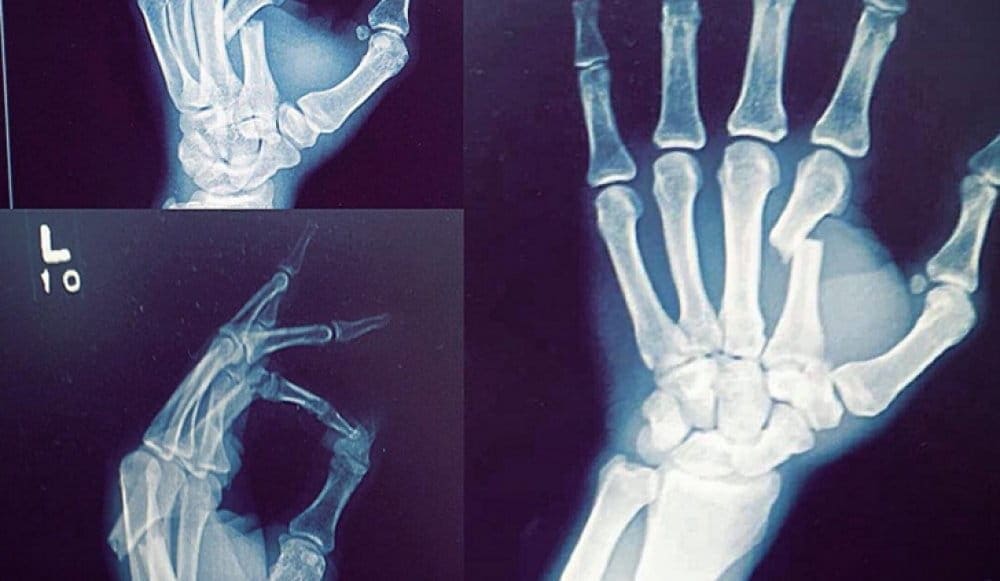

«Доктор мне сказал, что это один из худших преломов, которые он когда-либо видел. А теперь представьте, если бы я не сломал руку в первом раунде», - написал Штраус в Инстаграм, подтвердив свои слова рентгеновским снимком.